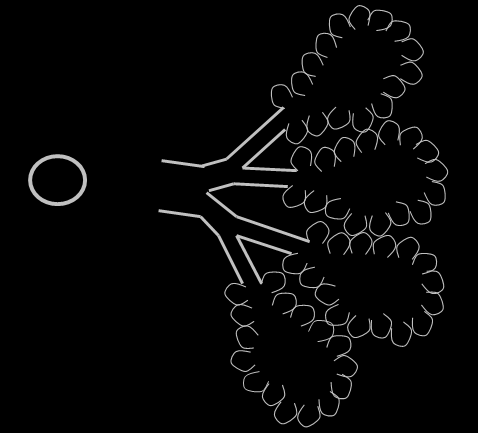

Discuss lung fields on radiographs?

Normal appearance – there are 6 lung lobes in dogs and cats, we don’t see individual lobes on radiographs, just see lung field

Divide into concentric circles

Describe these concentric circles in regards to lung fields?

Central, middle and peripheral thirds

Central – will see airway and BV markings

Middle – BV markings

Peripheral – not much in way of lung markings at all

Lung pattern or

normal lung markings??

Bronchial (parallel walls with lucent centre)

Vascular BV in transverse as circles or as branching linear structures with no air in the middle